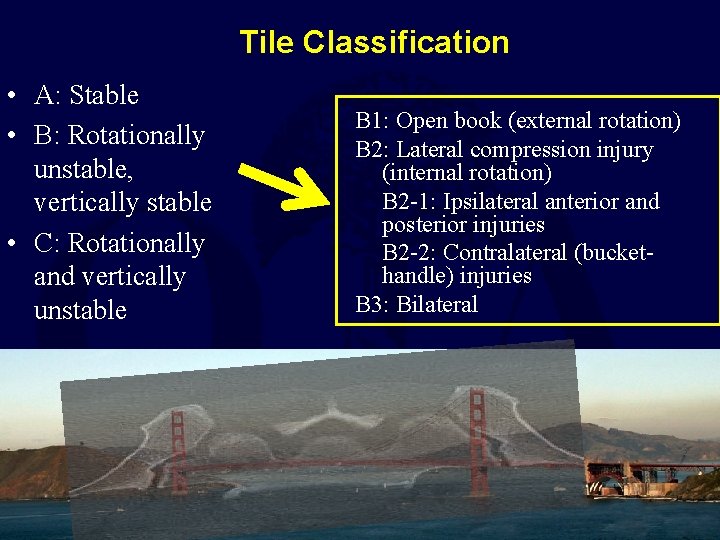

Tile Classification • A: Stable • B: Rotationally unstable, vertically stable • C: Rotationally and vertically unstable B 1: Open book (external rotation) B 2: Lateral compression injury (internal rotation) B 2 -1: Ipsilateral anterior and posterior injuries B 2 -2: Contralateral (buckethandle) injuries B 3: Bilateral